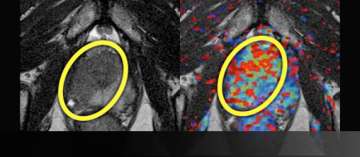

6) Dynamic Contrast-Enhancement for Biochemical Failure

- Elevated PSA after prostatectomy